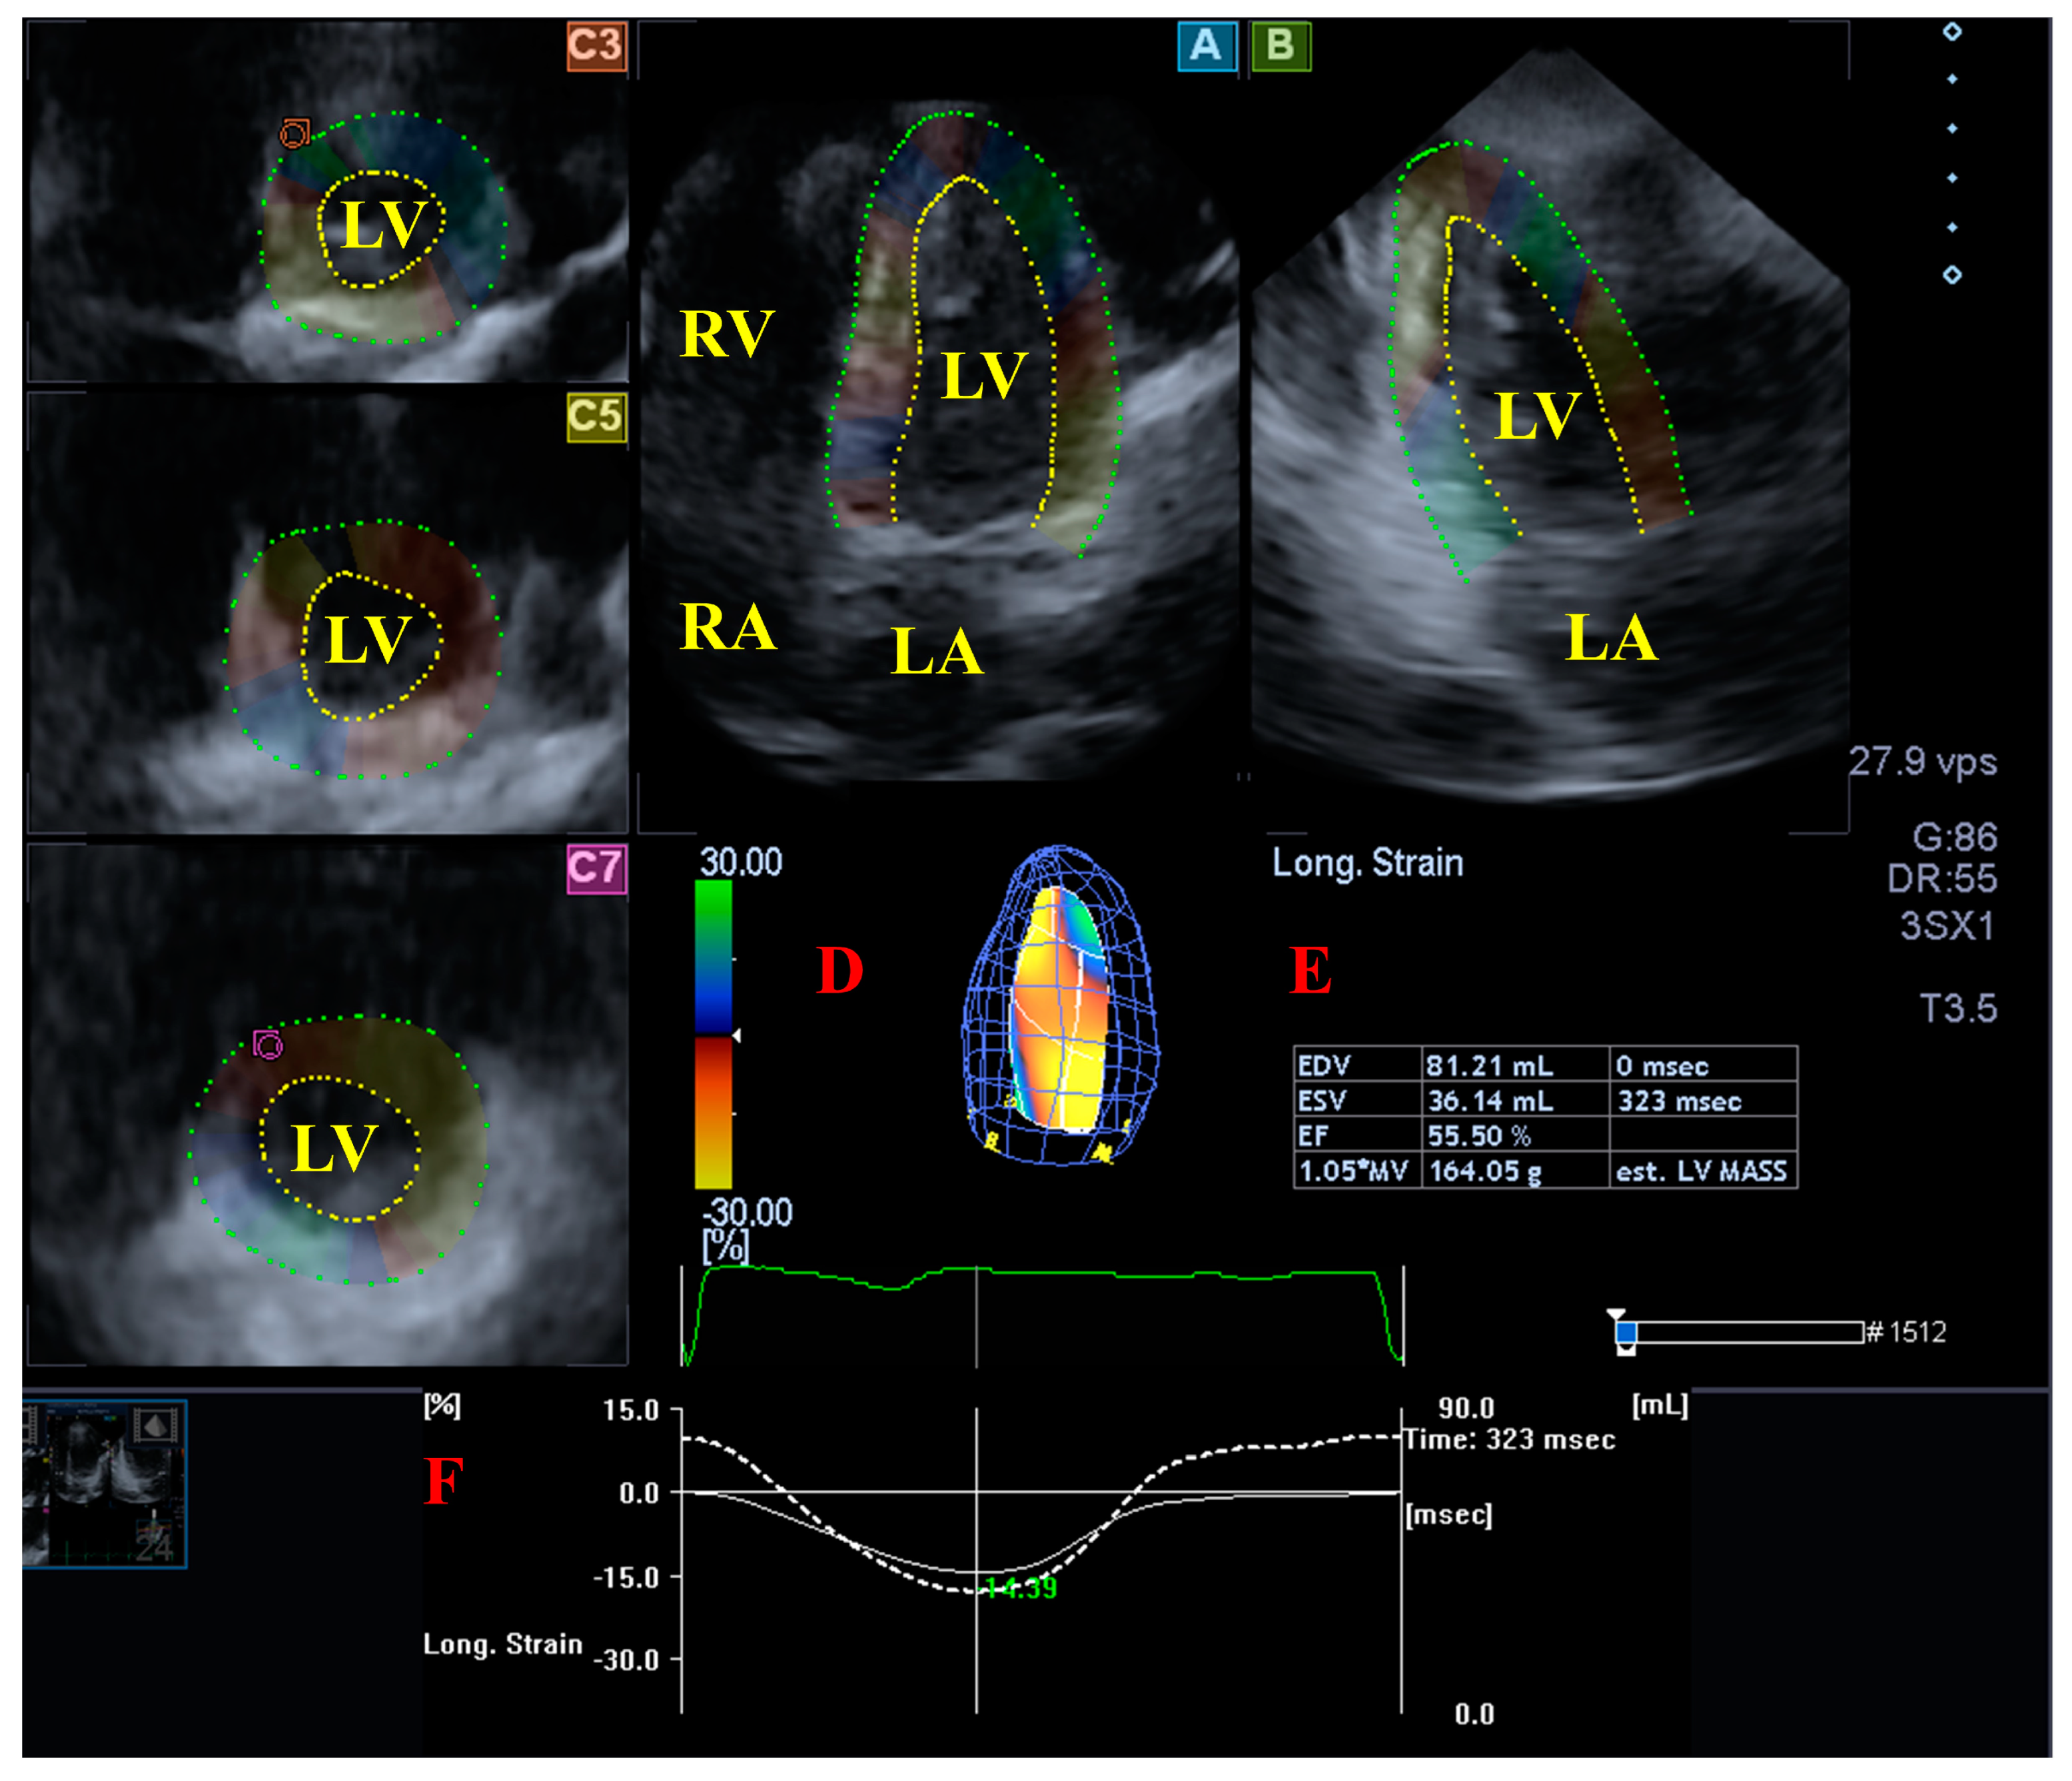

2.4. Three-Dimensional Speckle-Tracking Echocardiography